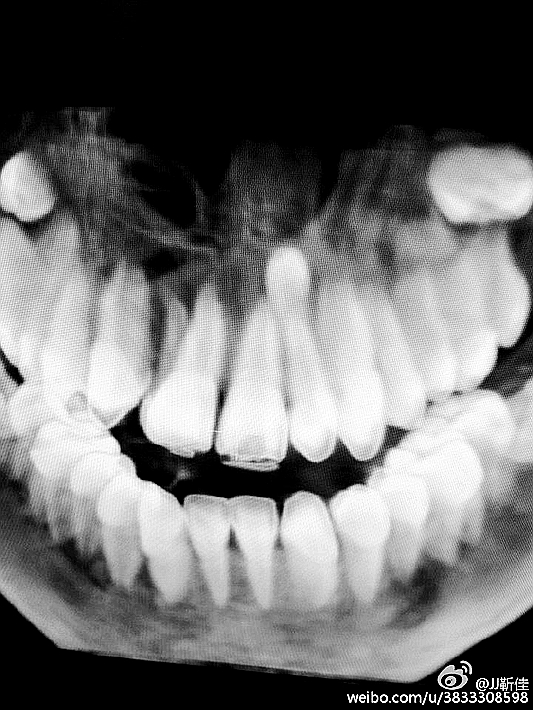

今年的額外牙真多啊 男孩14周。

額外牙拔除

好大的額外牙